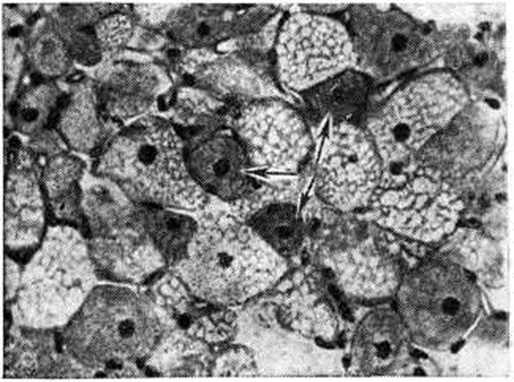

На разрезе опухоль буроватого цвета с чёткими очертаниями, дольчатого строения. Микроскопически состоит из крупных округлых или полигональных клеток с чёткими границами и центрально расположенными ядрами (рисунок 1). Клетки группируются в ячейки или дольки окружённые нежной стромой. Различают два вида клеток: одни с гомогенной, окрашивающейся в тёмно-розовый цвет цитоплазмой, содержащей небольшое количество жира, другие — мелкозернистые или пенистые, перегруженные липидами (нейтральным жиром, холестерином. |